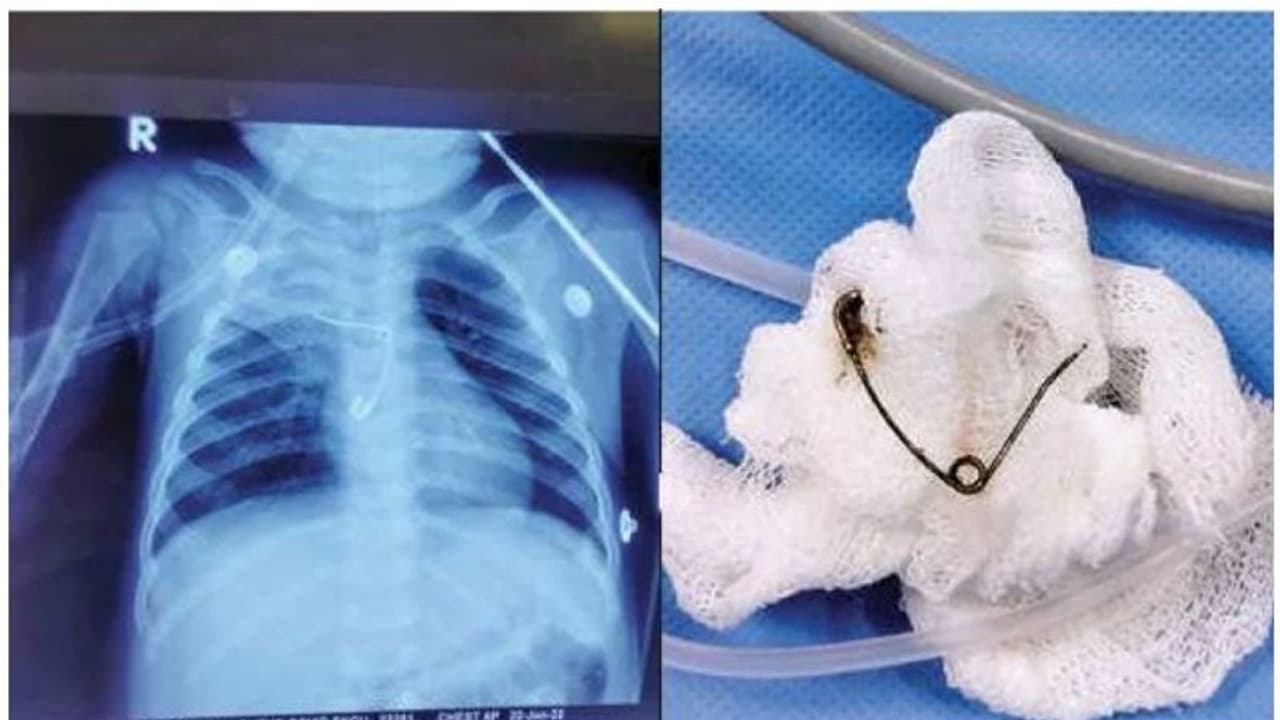

തൃശൂര്: സേഫ്റ്റി പിന് (Safety pin) വിഴുങ്ങി ജീവന് അപകടത്തിലായ എട്ടുമാസം പ്രായമുള്ള ആണ്കുട്ടിയെ ശസ്ത്രക്രിയയിലൂടെ (Surgery) ജീവിതത്തിലേക്ക് തിരിച്ചുകൊണ്ടുവന്നു. തൃശൂര് മെഡിക്കല് കോളേജിലാണ് (Thrissur Medical college) മണ്ണുത്തി വല്ലച്ചിറവീട്ടില് വിനോദിന്റെയും ദീപയുടെയും മകനായെ ആണ്കുട്ടിക്ക് ചികിത്സ നല്കിയത്. ജനുവരി 19ന് രാത്രിയാണ് കുഞ്ഞിനെ മെഡിക്കല് കോളേജില് ചികിത്സയ്ക്കെത്തിച്ചത്. നേരത്തെ സ്വകാര്യ ആശുപത്രിയിലായിരുന്നു ചികിത്സ. ആശുപത്രിയില് എത്തുന്നതിനും രണ്ടാഴ്ചമുന്പെങ്കിലും സേഫ്റ്റിപിന് വിഴുങ്ങിയെങ്കിലും വൈകിയാണ് അറിയുന്നത്.

ബോധരഹിതമായ അവസ്ഥയിലാണ് കുഞ്ഞിനെ ആശുപത്രിയില് എത്തിച്ചത്. ഉടന് വെന്റിലേറ്ററിലേക്ക് മാറ്റി. പരിശോധനയ്ക്കിടെ തലച്ചോറില് പഴുപ്പ് കണ്ടെത്തി. ശസ്ത്രക്രിയക്കൊരുങ്ങിയ സമയത്താണ് കുട്ടിക്ക് കൊവിഡ് സ്ഥിരീകരിച്ചപിന്നീട് കൊവിഡ് ഐസിയുവിലേക്ക് മാറ്റി. കൊവിഡ് നെഗറ്റീവായ ശേഷം ന്യൂറോ സര്ജറി വിദഗ്ധര് തലച്ചോറിലെ പഴുപ്പ് നീക്കം ചെയ്തു. ഇതോടെ കുട്ടിയുടെ ആരോഗ്യനില മെച്ചപ്പെട്ടു. പിന്നീട് നടത്തിയ വിശദപരിശോധനയില് അന്നനാളത്തില് സേഫ്റ്റി പിന് കുടുങ്ങിക്കിടക്കുന്നതായി കണ്ടെത്തി. ഉടന് ശിശുരോഗ ശസ്ത്രക്രിയാവിഭാഗത്തിന്റെ നേതൃത്വത്തില് കുഞ്ഞിനെ അടിയന്തരശസ്ത്രക്രി ചെയ്ത് പിന് പുറത്തെടുത്തു. തുറന്ന നിലയിലായിരുന്നു സേഫ്റ്റി പിന് കുടുങ്ങിക്കിടന്നത്. അന്നനാളത്തിലെ പഴുപ്പും നീക്കം ചെയ്തു. സേഫ്റ്റി പിന് അന്നനാളത്തില് കുടുങ്ങിയതിനെത്തുടര്ന്നുണ്ടായ പഴുപ്പാണ് തലച്ചോറിലേക്കും വ്യാപിച്ചതെന്ന് ഡോക്ടര്മാര് പറഞ്ഞു. സേഫ്റ്റിപിന്നും നീക്കം ചെയ്തതോടെ കുട്ടി അപകടനില തരണം ചെയ്തു. ഇപ്പോള് ഭക്ഷണം കഴിക്കുന്നുണ്ട്. അടുത്ത പത്ത് ദിവസത്തിനുള്ളില് ആശുപത്രി വിടാനാകുമെന്നും ഡോക്ടര്മാര് പ്രത്യാശ പ്രകടിപ്പിച്ചു.

ന്യൂറോ സര്ജറി വിഭാഗം മേധാവി ഡോ. ആര്. ബിജുകൃഷ്ണന്, ഡോ. ജിയോ സനില്, ഡോ. ജിതിന്, ഡോ. അമോല് ഡാഗെ, ഡോ. ഷാഹിദ്, ശിശുരോഗ ശസ്ത്രക്രിയാവിഭാഗത്തിലെ ഡോ. ശശികുമാര്, ശിശുരോഗവിഭാഗത്തിലെ ഡോ. ടി.എ. ഷീല, ഡോ. ദീപ അനിരുദ്ധന് എന്നിവരുടെ നേതൃത്വത്തിലാണ് കുഞ്ഞിന് ചികിത്സ നല്കിയത്. മെഡിക്കല് കോളേജിലെ ഡോക്ടര്മാരുള്പ്പെടെയുള്ള ജീവനക്കാരോട് പറഞ്ഞറിയിക്കാനാകാത്തെ നന്ദിയുണ്ടെന്് അമ്മ ദീപ പറഞ്ഞു. സ്വന്തം കുഞ്ഞിനെ പരിചരിക്കുന്നതുപോലെയാണ് കുഞ്ഞിനെ ചികിത്സിച്ചതെന്നും ീപ പറഞ്ഞു. മണ്ണുത്തിയില് വാടകയ്ക്കാണ് ദീപയും കൂലിപ്പണിക്കാരനായ ഭര്ത്താവ് വിനോദും താമസിക്കുന്നത്.